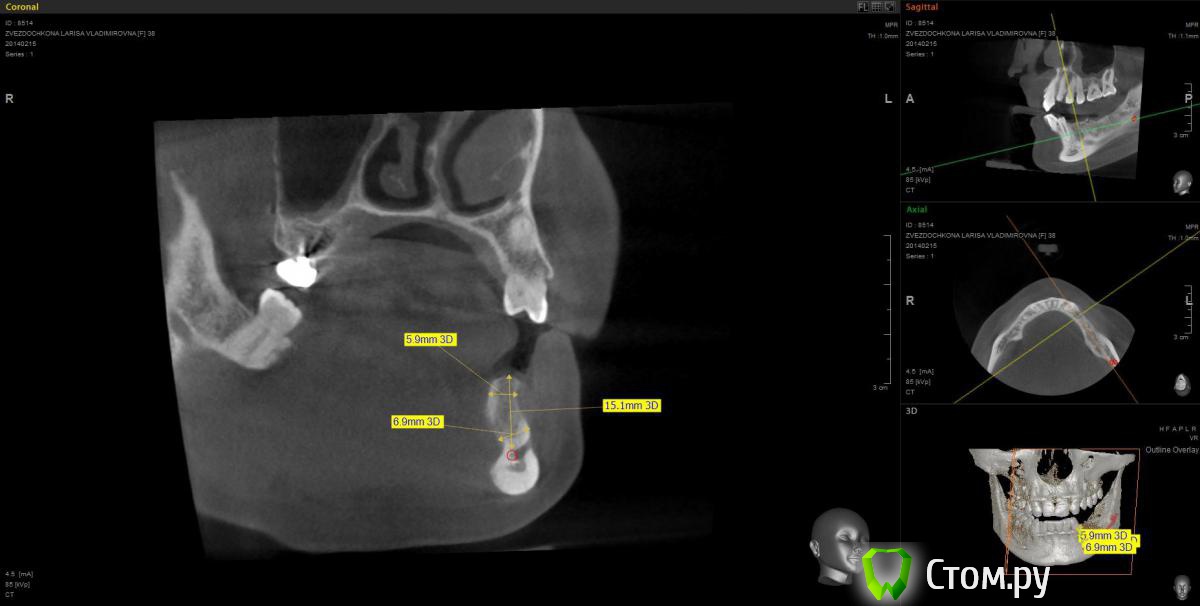

mapmax Опубликовано 3 марта, 2014 Поделиться Опубликовано 3 марта, 2014 Итак,коллеги,нуждаюсь в Вашем совете. У пациентки концевой дефект в обл 34 35 36 37, в периапикальной обл. 34 был воспалительный процесс который обострился и осенью прошлого года зуб был удален(не мной). Сейчас стоим перед имплантацией. Я рекомендую ставить импланты в обл отсутствующих зубов,но по финансовым соображениям пациентка настаивает на операции в обл 34 35 и позже в обл 36 37. Система выбрана Штрауманн SP SLActiv. Из за особенностей формы альвеолярного отростка в обл. 34 35( S-образная) и недавнего удаления 34 я рассматриваю установку импланта с язычным наклоном размера 4.8х10 RN в обл 35 RN 4.8х12. Но есть опасность оголения витков с вестибулярной стороны.Может все же сперва провести аугментацию "Аллопластом" с мембраной с вестибулярной стороны и отсрочено имплантация?! Срезы ДКТ прилагаю. Спасибо. Ссылка на комментарий

mapmax Опубликовано 5 марта, 2014 Автор Поделиться Опубликовано 5 марта, 2014 тоже склоняюсь к этому варианту.Тем более я чувствую в обл 3.4 киста, уж больно плотность костной ткани в этой обл.сомнительная. Ссылка на комментарий